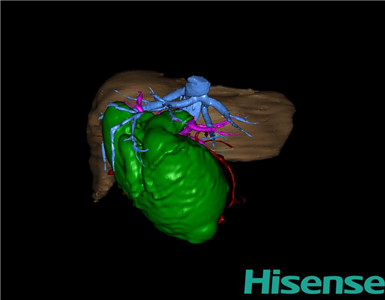

术前三维重建及手术方案设计:

将0.625mm双源薄层CT资料的静脉期和动脉期Dicom格式文件导入海信CAS系统。

通过调节窗宽窗位调整CT序号,对肝实质,胆囊,胆总管,下腔静脉,肝动脉、门静脉及肝静脉等进行三维重建;系统自动计算肝脏体积。

术前手术方案的规划。

术前三维重建:

重建图片